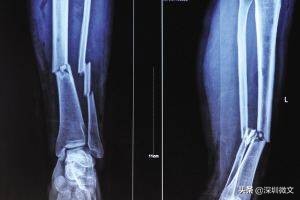

【X光:将人体骨骼投射到同一个平面上进行成像】

一、比方说某患者小腿出现明显骨折,那他骨折处对X光的吸收量就与周边骨干呈现出明显对比,骨折处就会出现一条明显的黑色裂痕。再者,医生也会通过白色“画成”的骨干是否有异常变形做判断。

X光一般是初筛,对体内异物的直观诊断。对于有移位骨折、有骨质改变的骨病、关节部位骨性病变、不透光异物存留、心肺器质性疾病、消化系统梗阻等疾病有很好的诊断价值。X光的优点是对于骨干病变的诊断,但对于体内的软组织检查没有太多效果。